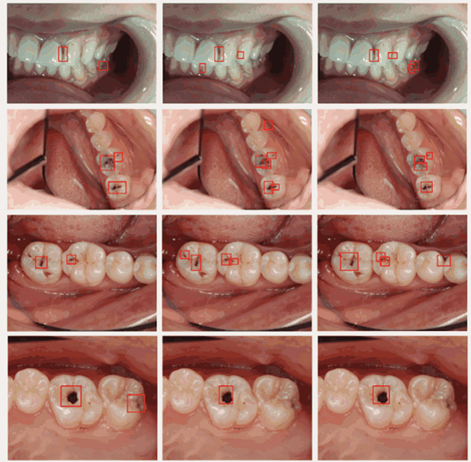

الشكل:[3] امثلة على كشف تسوس الاسنان في صور الاختبار.[9]

الشكل [7]: أمثلة لصور سريرية ونتائج الاختبار المقابلة لها باستخدام خوارزميات الذكاء الاصطناعي[20].